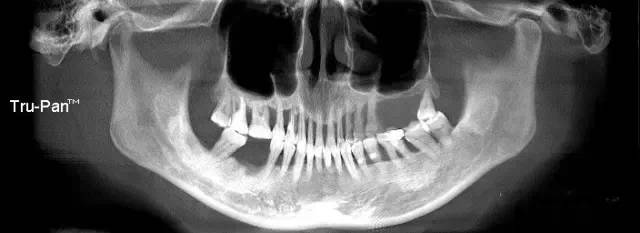

第三圖:上頜竇氣化導(dǎo)致上頜竇過大,上頜竇底骨質(zhì)向紙張一樣薄。只適合做外提升。